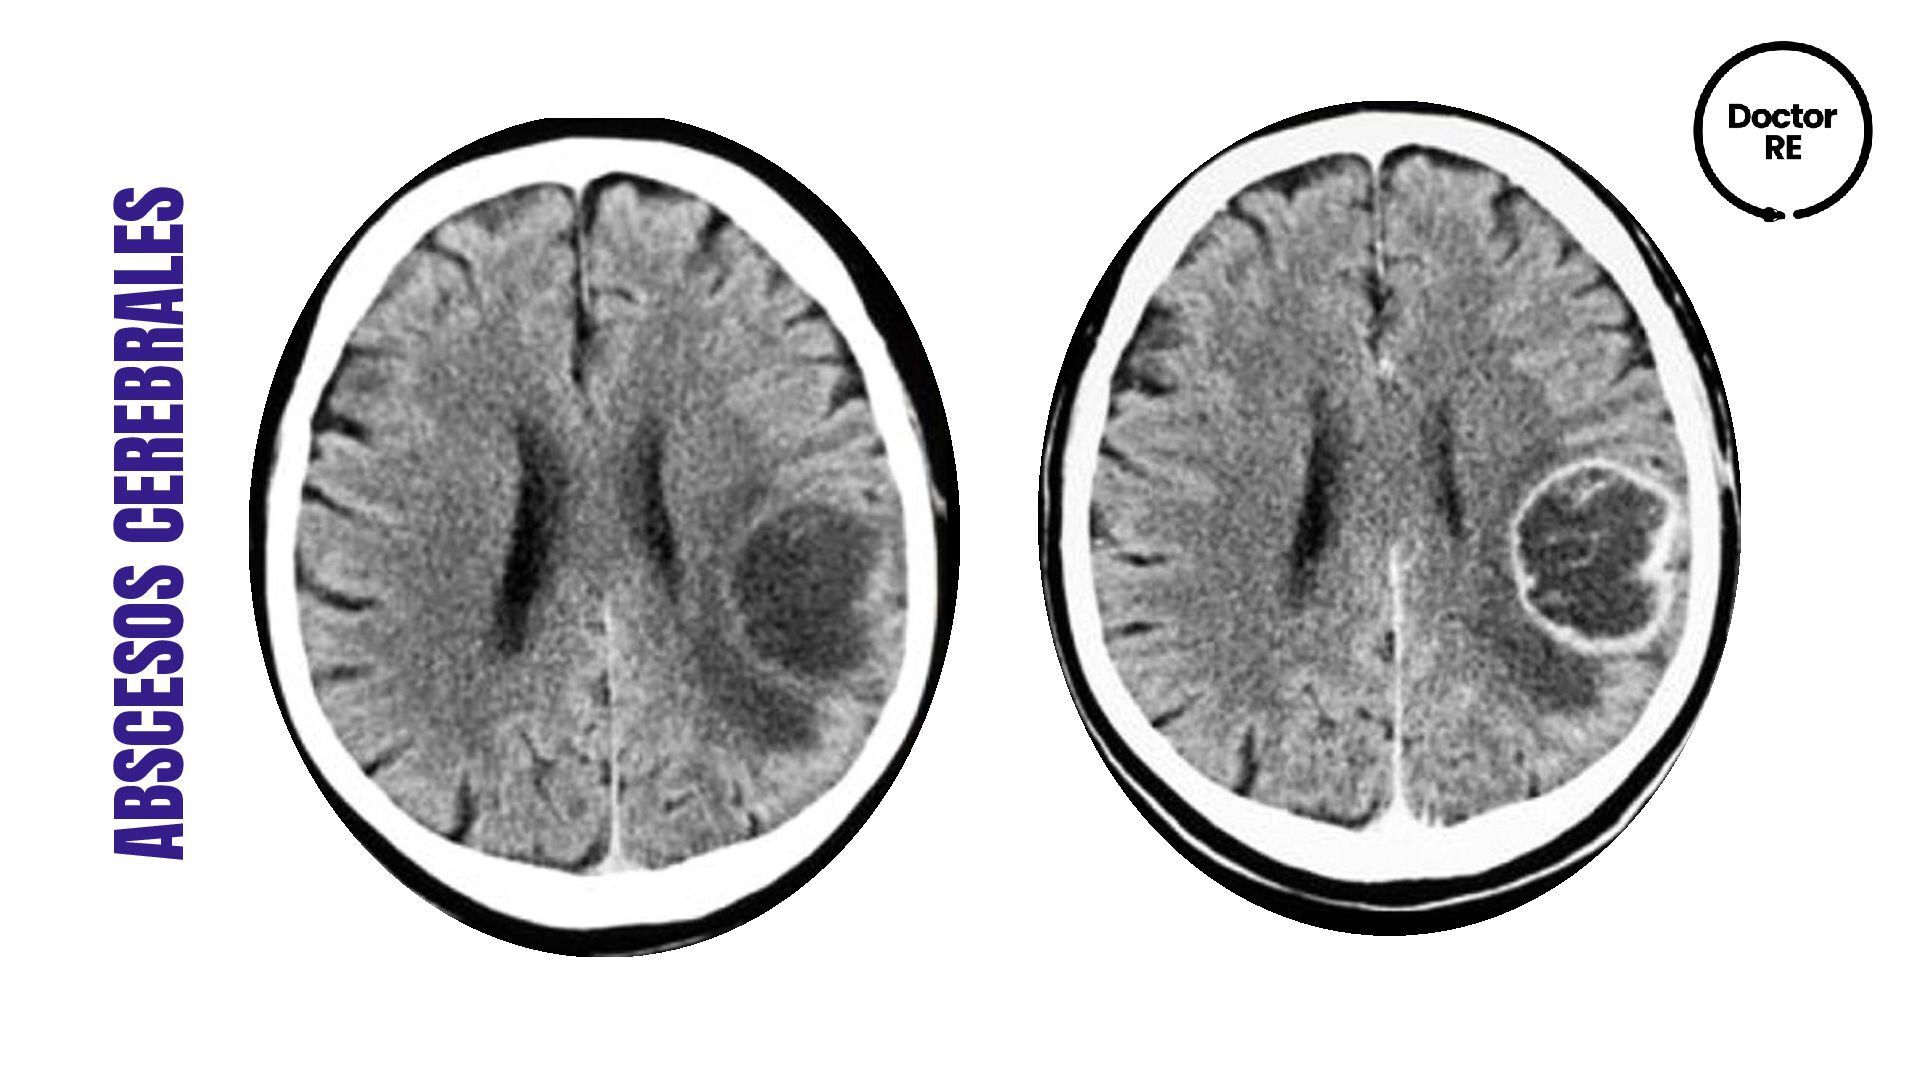

1. ABSCESOS CEREBRALES Proceso supurativo focal en el interior del parenquima

cerebral DEFINICIÓN 1er Fase de cerebritis 2° Formación de una cápsula de colágeno con gliosis pericapsular

Aspergillus fulmigatus •Inmunocomprometidos: Nocardia y toxoplasma ETIOLOGÍA: •CEFALEA •FIEBRE •FOCALIDAD NEUROLÓGICA (DÉFICIT O CONVULSIONES) CLÍNICA •TAC CON CONTRASTE (lesion hipodensa que capta el contraste en anillo) •RM mejor en fase cerebritis •Elevación VSG y PCR, leucocitosis DIAGNÓSTICO •CIRUGÍA EVACUADORA (ÚNICAS) Y ANTIBIÓTICOS (PENICILINA O CEFOTAXIMA + METRONODAZOL) (AUREUS: VANCOMICINA) •PAAF y Resección quirúrgica (TCE) •Dexametasona y anticomiciales sólo en presencia de crisis TRATAMIENTO